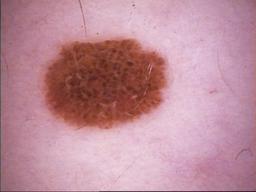

{

"age_approx": 60,

"anatom_site_general": "lower extremity",

"concomitant_biopsy": false,

"diagnosis_1": "Benign",

"diagnosis_2": "Benign melanocytic proliferations",

"diagnosis_3": "Nevus",

"diagnosis_4": "Nevus, NOS, Compound",

"diagnosis_confirm_type": "serial imaging showing no change",

"image_type": "dermoscopic",

"melanocytic": true,

"patient_id": "IP_5472658",

"sex": "female"

}